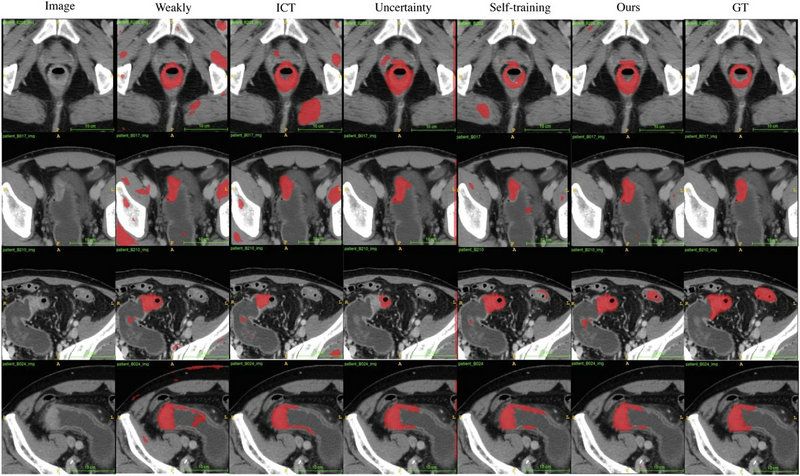

ÍŶÓʹÓÃÀ´×Ôngµç×ÓÓÎÏ·Á¥ÊôµÚÁùÒ½ÔººÍ¿¦µØÒ»ÔºµÄ923ÀýÓбê×¢½á³¦°©CTÓ°ÏñºÍ2670ÀýÎÞ±ê×¢½á³¦°©CTÓ°Ïñ×÷ΪSOUSA¿ò¼ÜµÄѵÁ·Êý¾Ý¼¯£¬£¬£¬²¢Ê¹ÓÃ417Àý½á³¦°©CTÓ°Ïñ¶ÔSOUSA¿ò¼Ü¾ÙÐÐÑéÖ¤£¬£¬£¬Ð§¹ûÏÔʾÆä×Ô¶¯Ö§½âЧ¹ûÓÅÓÚÏÖÓеÄÈõ¼àÊӺͰë¼àÊÓѧϰģ×Ó¡£¡£¡£ÓëÏÖÔÚ×îÏȽøµÄÒªÁìICT (Verma et al.£¬£¬£¬2019)¡¢¡¢²»È·¶¨ÐÔ¸ÐÖª(Yu et al.£¬£¬£¬2019)ºÍ×ÔÎÒѵÁ·Ïà±È£¬£¬£¬SOUSA¿ò¼ÜÔÚÿ¸öÊý¾Ý±ÈÂÊÉ϶¼µÖ´ïÁË×î¼ÑÐÔÄÜ¡£¡£¡£±ðµÄ£¬£¬£¬µ±Êý¾Ý¼¯µÄ¾ÞϸÓÐÏÞʱ£¬£¬£¬SOUSA¿ò¼ÜµÄÐÔÄÜÉõÖÁÓëʹÓÃ÷缯עÊ͵ÄÄ£×ÓµÄÐÔÄÜÏ൱¡£¡£¡£

¶Ô³¦°©Êý¾Ý¼¯Ê¹Óòî±ðÒªÁìµÄ×Ô¶¯Ö§½âЧ¹û